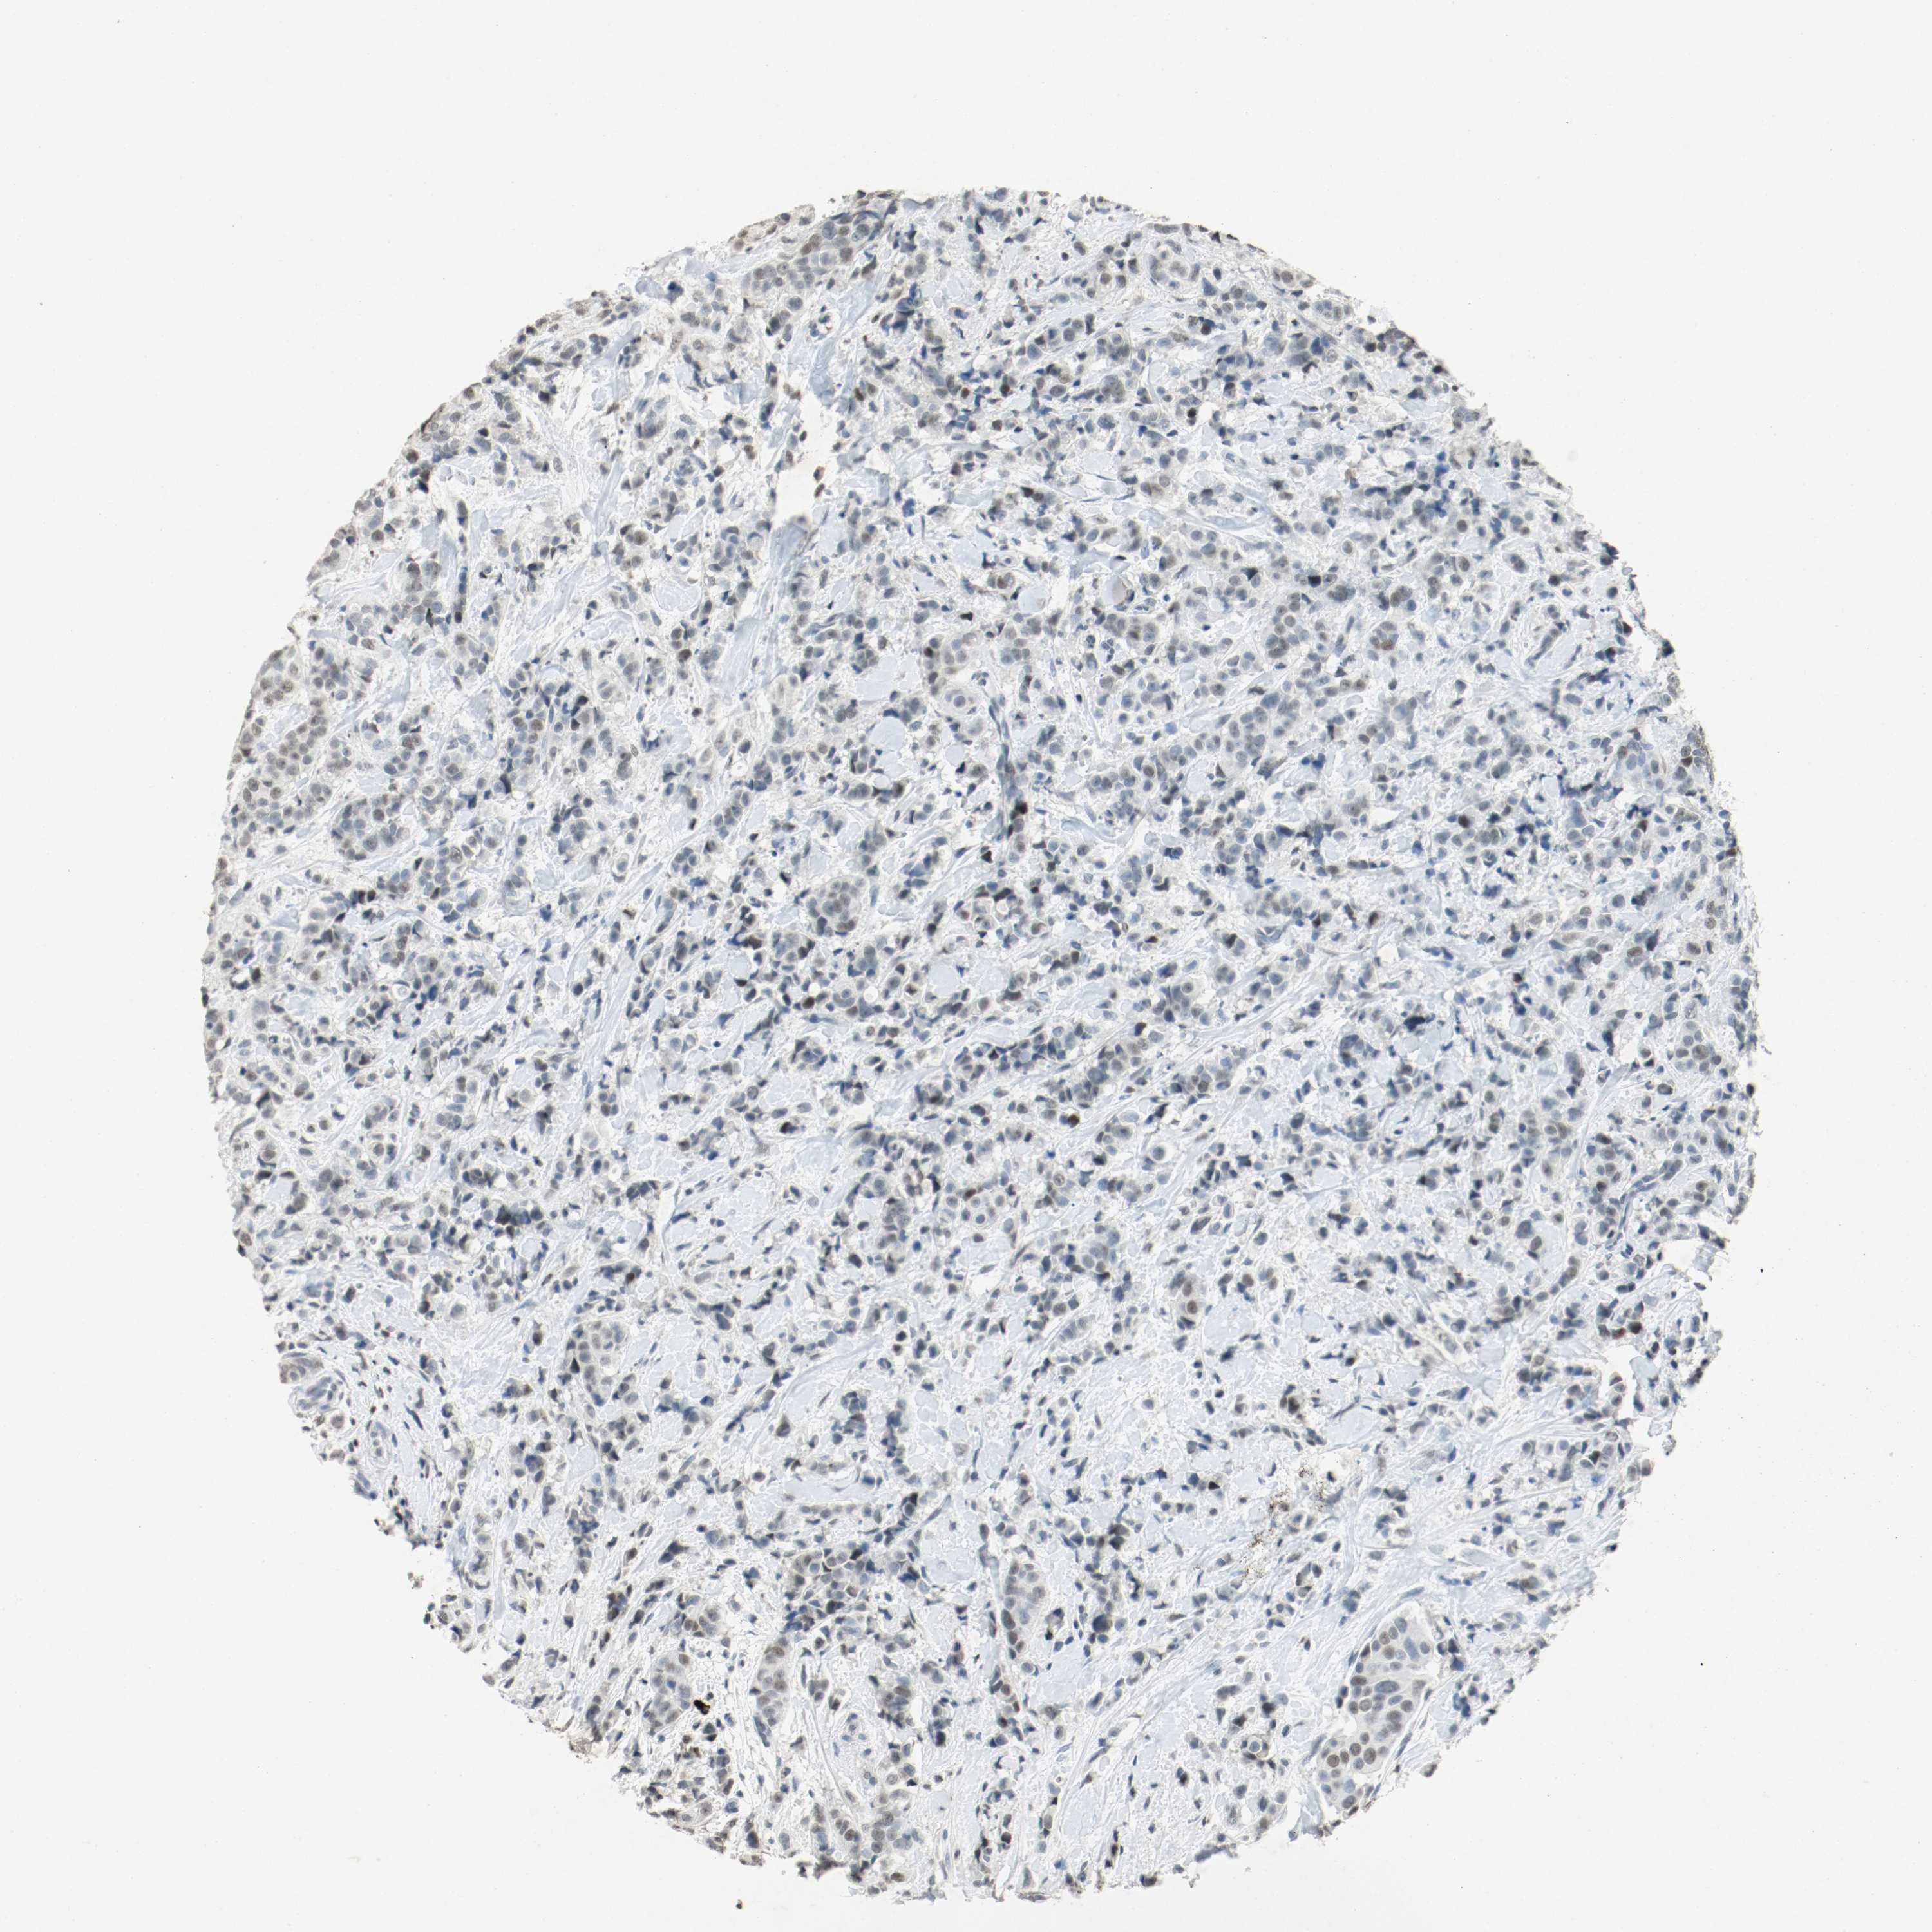

BRCA TCGA BRCA VALIDATION PROTEIN EXPRESSION

Breast cancer

Human cancer